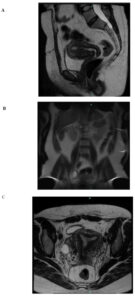

A 35-year-old nulligravid woman presented in late 2023 with abnormal uterine bleeding and chronic pelvic pain. A transvaginal ultrasound performed in 2019 documented a large hypoechoic intramural mass measuring approximately 12 × 10 × 8 cm (≈ 2,000 cm³) and a uterine volume of 330 cm³. Magnetic resonance imaging (MRI) in 2020 confirmed uterine enlargement (15 × 15 × 11 cm) with associated pelvic varices.

Follow-up transvaginal ultrasound on August 8, 2023, demonstrated a retroverted uterus measuring 7.0 × 6.5 × 6.0 cm (volume 143 cm³), with a pedunculated subserosal leiomyoma measuring 9.5 × 8.0 × 6.0 cm (volume ≈ 283 cm³). The endometrium was linear and uniform, measuring 8 mm in thickness. The right ovary was normal (6.5 cm³), while the left ovary contained a simple cyst measuring 63 × 68 × 58 mm (≈ 4.1 cm³).

Family history was not available for this patient, which limited the possibility of assessing hereditary patterns within the family. The patient was referred to the oncology service for long-term surveillance. Abdominal and pelvic MRI in October 2024 showed no evidence of recurrence or postoperative complications. Expected postsurgical pelvic changes were observed, as well as a small periurethral cyst (1.2 cm) of no clinical relevance and a fat-containing umbilical hernia without incarceration or inflammation. Based on these findings, the plan was continued observation with the possibility of discharge from oncology follow-up if stability was maintained.